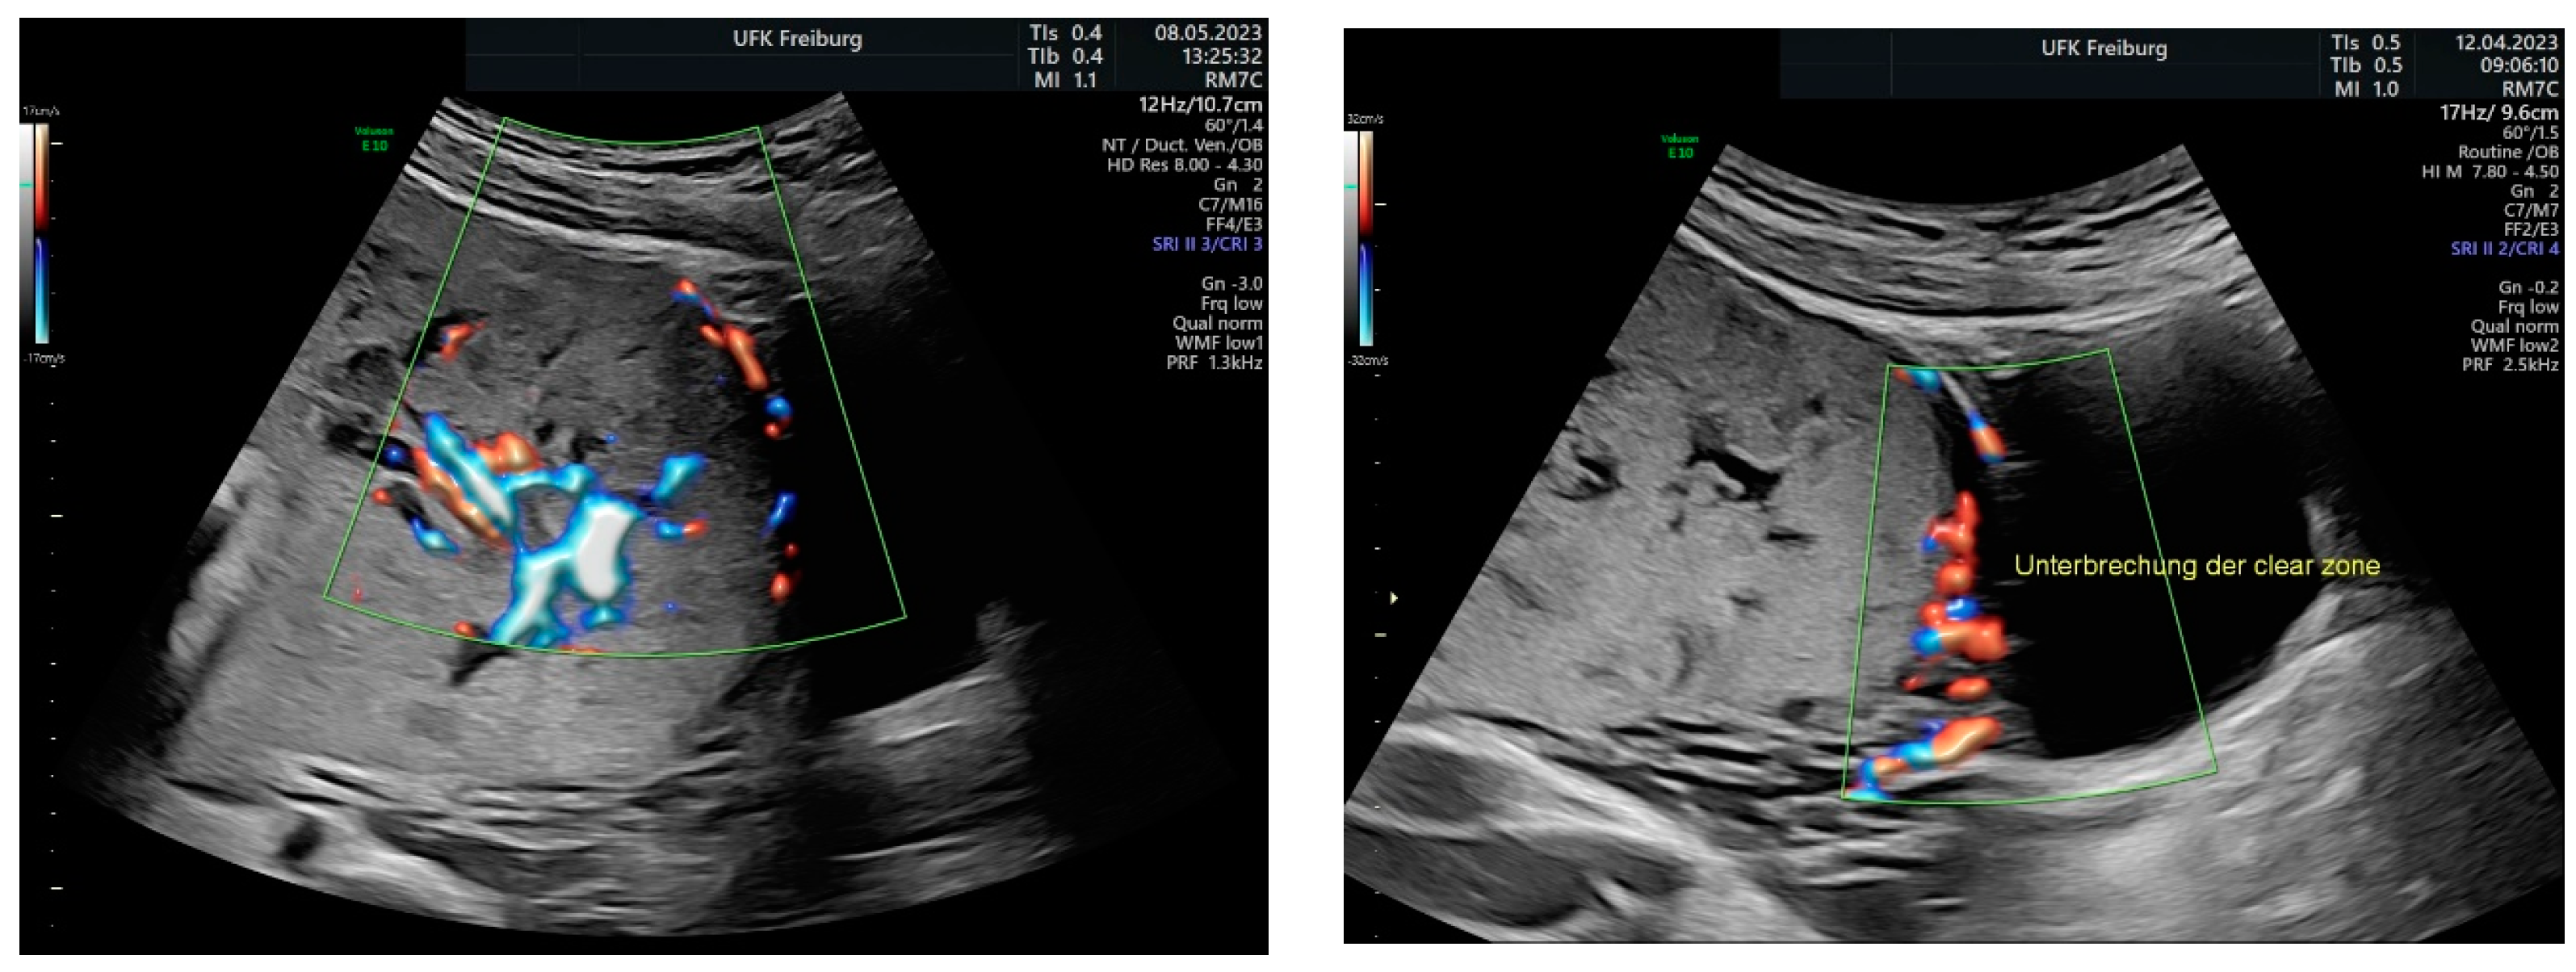

Sonographic findings (Figure 11):

Figure 11.

Increased placental blood flow on 2D ultrasound. Red color represents increased placental blood flow moving to the transducer; blue color represents placental blood flow moving leaving away from the transducer.

Sonographic findings (Figure 13):

Figure 13.

According to the standardized description of the European Working Group on Abnormally Invasive Placenta for ultrasound anomalies, the following anomalies may be seen: Loss of the “clear zone”—partially more in the middle (N/3):

- Abnormal placental lacunae;

- No interruption of the echoic bladder wall Myometrial thinning;

- No protrusion of the placenta into the bladder wall;

- No uterovesical hypervascularization;

- Subplacental hypervascularization.